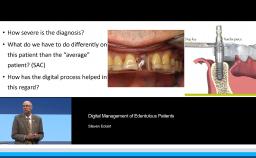

The lecture reviews the digital possibilities to design esthetics and thereby control the esthetic outcome in implant dentistry. The presentation begins with a discussion of the most frequently used criteria to define treatment success in implant dentistry. Clinical cases demonstrate how digital technologies allow planning in three dimensions for optimal esthetics. Practical methods to measure esthetic outcomes are also provided, based on four parameters: implant placement, soft tissue management, prosthetic considerations, and patient satisfaction.

- explain success criteria for implant esthetics